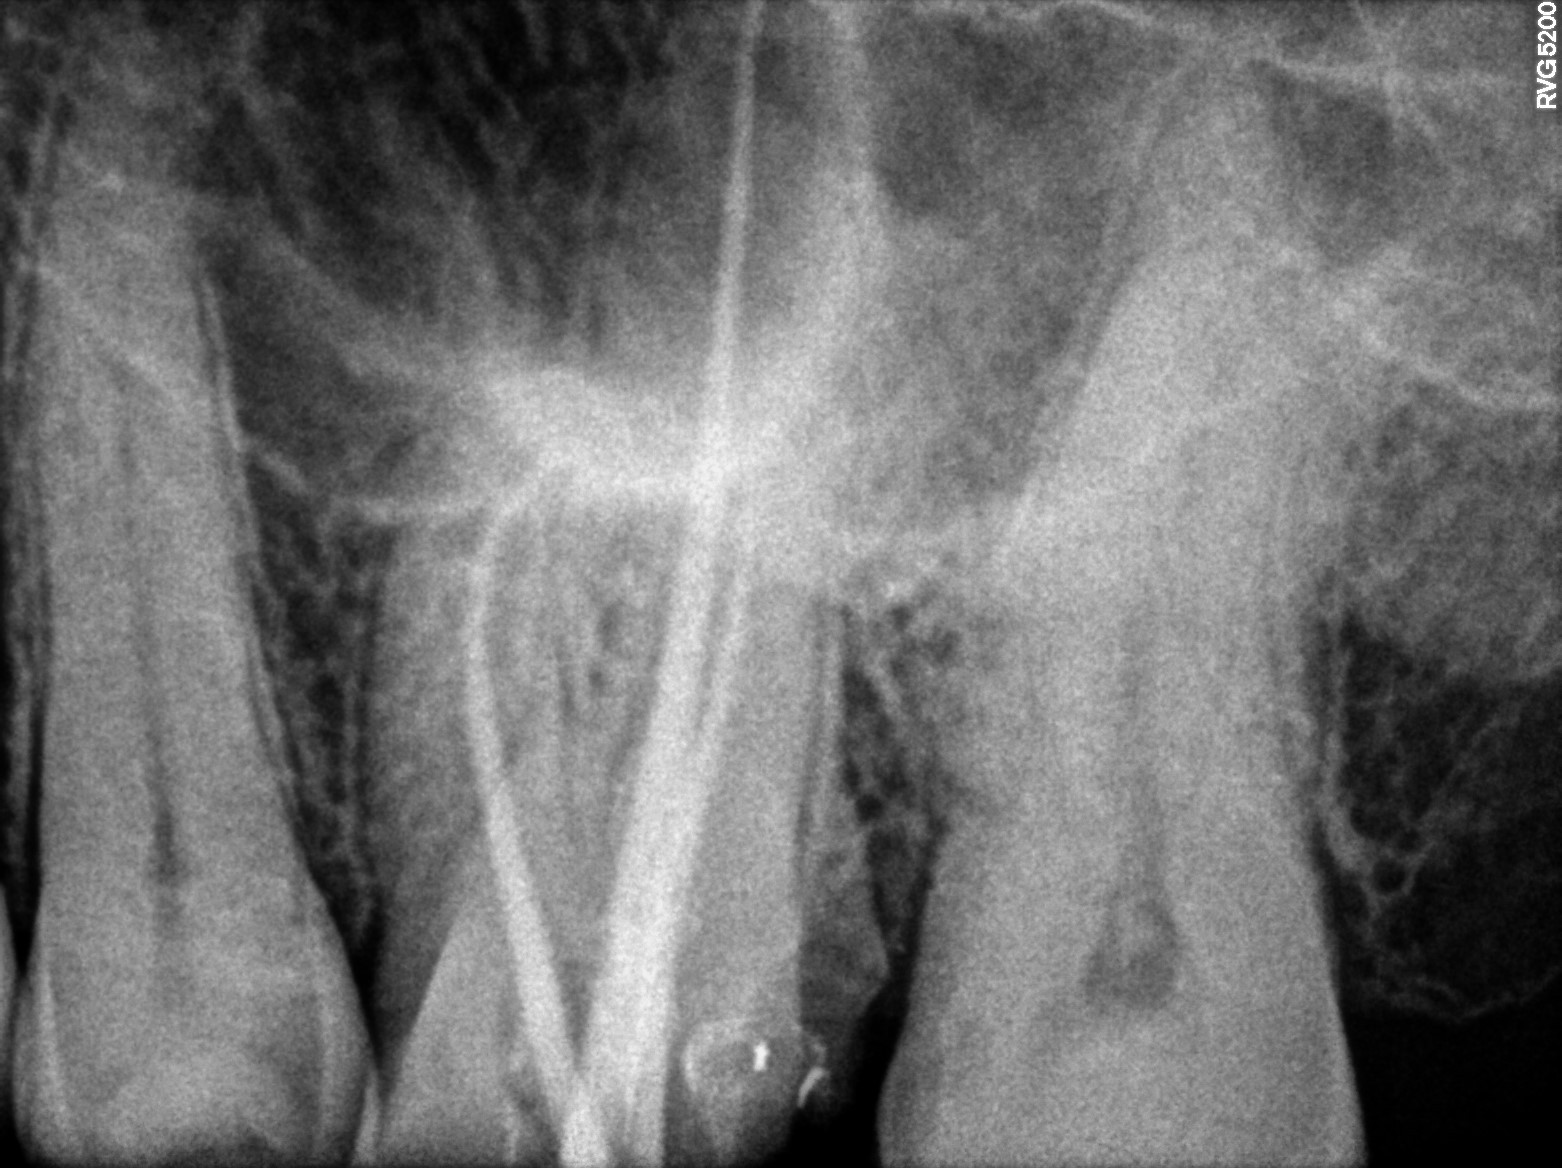

Dental Radiographs FHIR: DocumentReference · LOINC 24641-7

xray_1747409705_1.jpg

24641-7